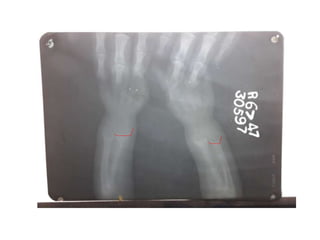

SCURVY

• Generalised osteopenia

• cortical thinning: “pencil-point” cortex

• Periosteal reaction due to subperiosteal

haemorrhage

• scorbutic rosary: expansion of the

costochondral junctionsmay relate to the

fracturing of the zone of provisional

calcification during normal respiration

• similar to the rachitic rosary appearance as

seen in rickets

• Haemarthrosis

• Wimberger ring sign: circular, opaque

radiologic shadow surrounding epiphyseal

centres of ossification, which may result

from bleeding

• Frankel line: dense zone of provisional

calcification

• Trümmerfeld zone: lucent metaphyseal band

underlying Frankel line

• Pelken spur: metaphyseal spurs which result

in cupping of the metaphysis

SCURVY • Generalised osteopenia •cortical thinning: “pencil-point” cortex • Periosteal reaction due to subperiosteal haemorrhage • scorbutic rosary: expansion of the costochondral junctionsmay relate to the fracturing of the zone of provisional calcification during normal respiration • similar to the rachitic rosary appearance as seen in rickets • Haemarthrosis • Wimberger ring sign: circular, opaque radiologic shadow surrounding epiphyseal centres of ossification, which may result from bleeding • Frankel line: dense zone of provisional calcification • Trümmerfeld zone: lucent metaphyseal band underlying Frankel line • Pelken spur: metaphyseal spurs which result in cupping of the metaphysis